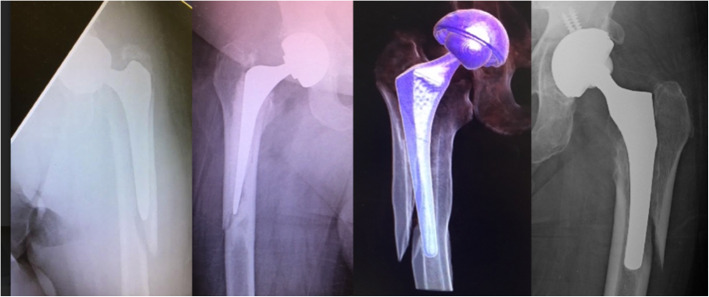

An additional observation of this study was that the Vancouver B2 classification consists of four distinct fracture patterns: the previously described comminuted ‘burst’, clamshell and spiral patterns and the newly observed ‘reverse’ clamshell pattern. Description of these fracture patterns follows in the “Discussion” section, and representative X-ray appearances from this series are shown with accompanying graphic depictions in Fig 1. The comparative association of these fracture patterns with each stem type is shown in Table 4. Burst and spiral fracture patterns were significantly associated with cemented stems whereas the clamshell fracture pattern was significantly associated with uncemented stems. The reverse clamshell pattern occurred similarly in both stems. The association of Vancouver classification subtypes including the four B2 fracture patterns listed above with respect to stem geometry (Table 5) reflected the overall trend of fracture patterns.

Fig. 1.

Vancouver B2 fracture patterns: 1.1 burst, 1.2 clamshell, 1.3 reverse clamshell, and 1.4 spiral

In radiographically analysing a large series of periprosthetic fractures, a consistent fracture pattern not previously described in the literature was observed. This fracture originates in the medial calcar and exits through the lateral cortex with an intact medial cortex. This fracture is named the ‘reverse’ clamshell pattern and is recognised by this study as a commonly occurring Vancouver B2 fracture pattern. This name was chosen for two reasons: the first, that it is the mirror image of the ‘clamshell’ and the second, that it behaves similarly to a reverse oblique proximal femoral fracture, with similar supero-lateral displacement of the proximal fragment from abductor pull. This fracture occurs similarly in cemented and uncemented stems, and further radiographic examples from this series are shown in Fig. 2. Although it was not the aim of this study to investigate outcomes of treatment, reverse clamshell fractures were routinely managed in this series with revision arthroplasty to a distal bearing stem with either cerclage wire or plate fixation of the proximal fracture fragment. An example of a patient treated with this approach is shown in Fig. 3 demonstrating the achievement of union.

Fig. 3.

Surgical management of reverse clamshell fracture with revision arthroplasty and cerclage wire fixation